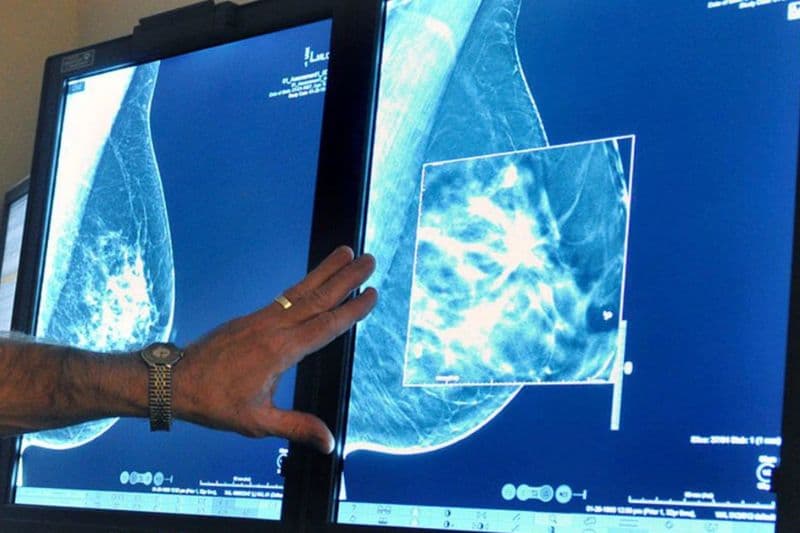

Chụp X-quang tuyến vú (mammography) là phương pháp sử dụng tia X liều thấp để ghi lại hình ảnh nhu mô vú, giúp phát hiện các tổn thương nhỏ mà thăm khám lâm sàng khó nhận biết. Theo khuyến cáo của Hiệp hội X-quang Hoa kỳ (American College of Radiology – ACR), phụ nữ có nguy cơ trung bình nên bắt đầu tầm soát từ tuổi 40 và thực hiện hàng năm. Nhiều trung tâm y tế học thuật hàng đầu Hoa Kỳ như Mayo Clinic hay Johns Hopkins Medicine cũng nhấn mạnh vai trò của mammogram trong phát hiện sớm ung thư vú, đặc biệt ở giai đoạn chưa có triệu chứng.